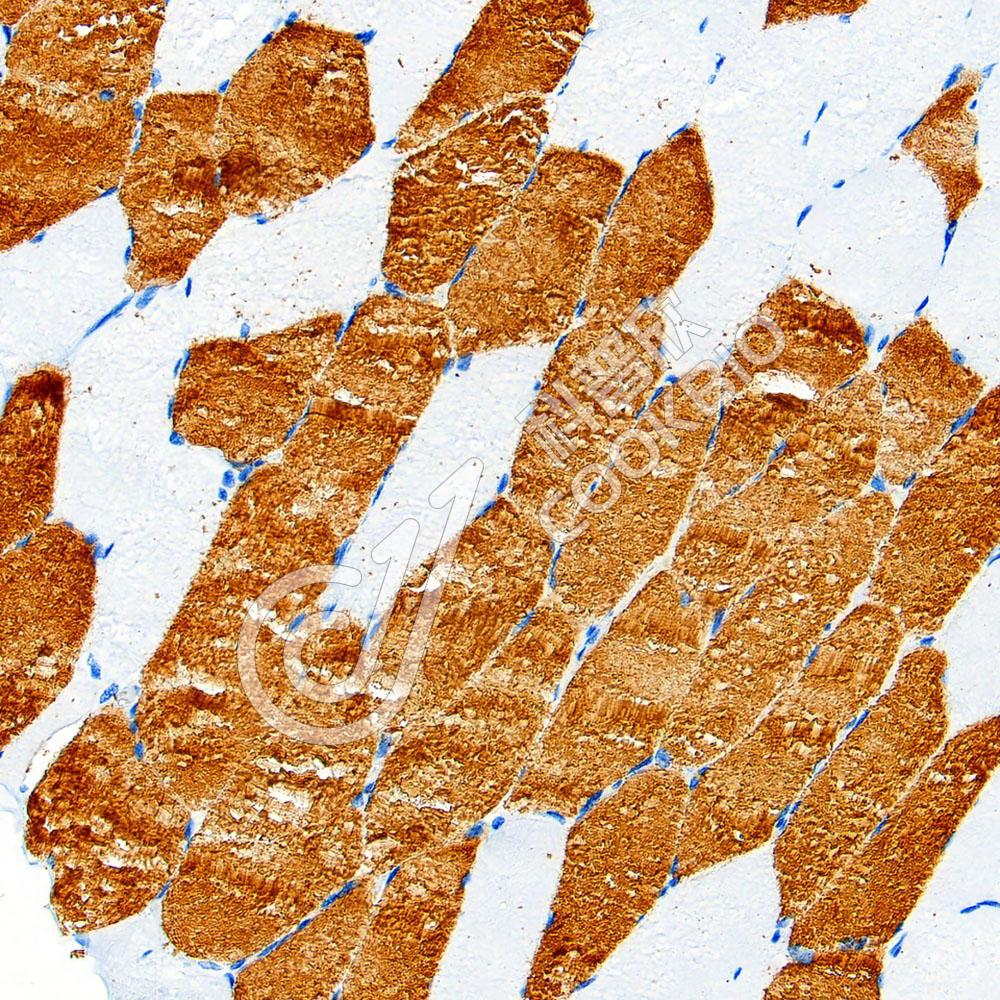

IHC检测PD-L1蛋白(货号 K5467208).

样品: 人肺癌, 4%多聚甲醛 (货号KSG1101) 固定12-24小时.

抗原修复: Tris-EDTA抗原修复液(pH 9.0) (KSG1203), 98℃, 20分钟.

—抗: 1: 300稀释, 4℃ 孵育过夜.

二抗: S-vision免疫组化多聚二抗(山羊抗兔),即用型 (货号KB3906), 室温孵育20分钟.